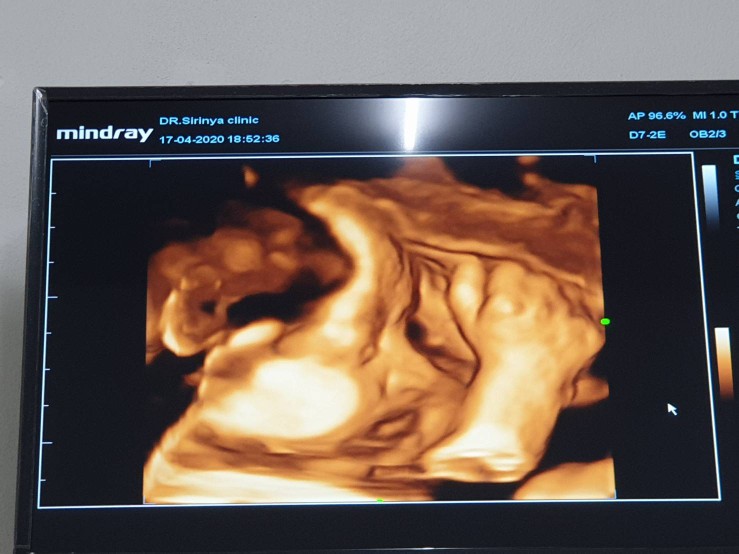

จมูกลูก

มีบ้านไหนซาวด์แล้วจมูกโด่งแบบนี้มั้ยคะ ออกมาจมูกน้องโด่งแบบนี้รึเปล่า? นี่คุณหมอบอกโด่งมาก?

โด่งมากค่ะแม่ ซาวด์ตอนกี่วีคคะ

แม่ซาวกี่วิคคะ เห็นชัดมากค่ะ